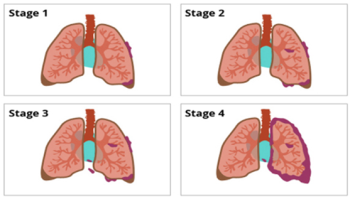

Ung thư phổi là một trong 3 loại ung thư thường gặp nhất và là nguyên nhân gây tử vong hàng đầu do ung thư ở phạm vi toàn cầu. Theo thống ...